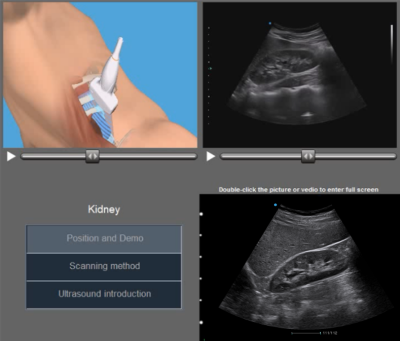

S-helper

embedded teaching software with 3D animation facilitates your practices.